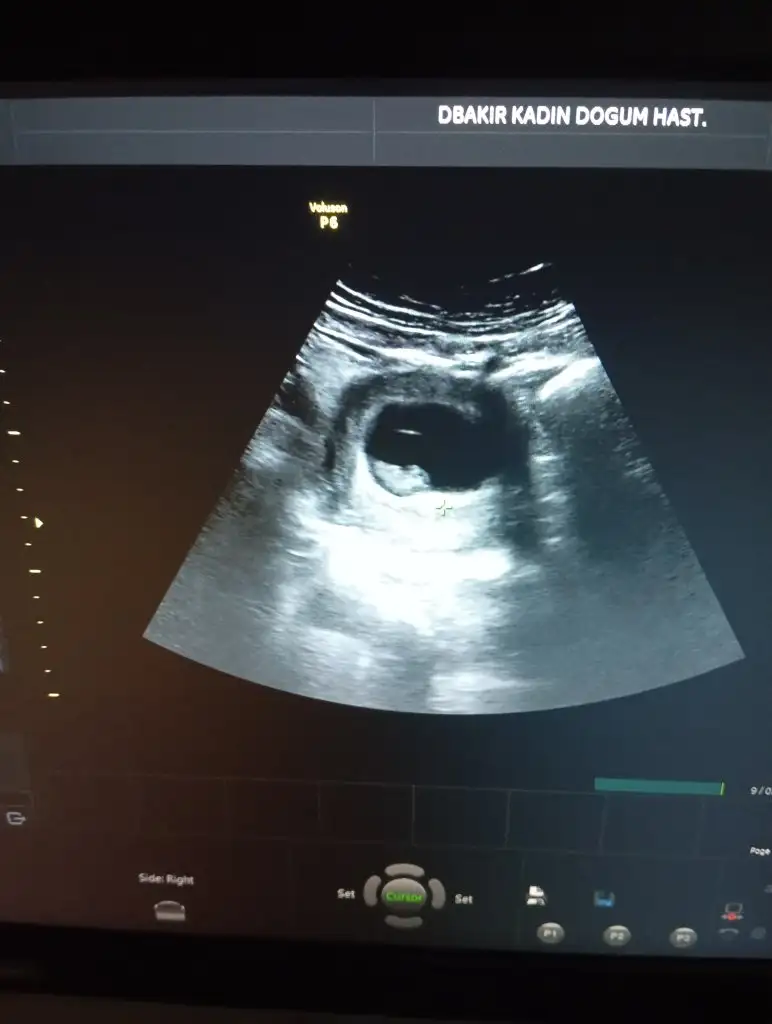

Rica edersem anlıyorsanız benimkine de bakarmisiniz

Merhaba anlıyorsanız benimkine de bakarmisiniz aceba

Sağlıklı bi şekilde kucağınıza alırsınız inşallah, doktor çıkıntı gördüm ama kordon da olabilir dedi yüzde 51 kız diyorum 52 olmaz dedi bize deSadece tahmin amabenim erkek dedi

Banada başta bir çıkıntı var dediler kızda olablr iki hafta sonra gttgmzde erkek dedilerSağlıklı bi şekilde kucağınıza alırsınız inşallah, doktor çıkıntı gördüm ama kordon da olabilir dedi yüzde 51 kız diyorum 52 olmaz dedi bize de